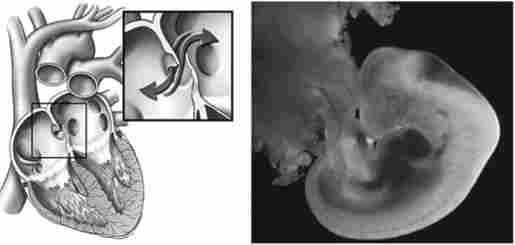

Серце розвивається з мезодерми у вигляді парної закладки на стадії одного-трьох сомітов - це відбувається приблизно на 17-й день розвитку зародка. Соміт (первинний сегмент) - парне метамерное освіту у зародків. Поділ серця на праву і ліву половини починається з кінця 3-го тижня завдяки одночасного зростання двох перегородок - з передсердя і верхівки шлуночка. Атріосептальний починає утворюватися з 4-го тижня внутрішньоутробного життя. Вона ділить первинне загальне атриовентрикулярное отвір на два: праве і ліве венозні отвори. На 6-му тижні в цій перегородці утворюється первинне овальний отвір (рис. 5.3). Виникає трикамерну серце з повідомленням міжпередсердями.

Серце плоду (виділено відкрите овальне вікно)

Рис.5.3. Серце плоду (виділено відкрите овальне вікно)

Серце плоду має свої особливості - відкриті овальне вікно, отвори між правим і лівим передсердями і артеріальна протока. Такі особливості будови серця сприяють надходженню кисню в усі органи і системи плоду, зменшують потік крові до легким, які під час перебування дитини в утробі матері не працюють, і одночасно збільшують потік крові до тканин і органів.

У плодовий період розвитку збагачена киснем кров з відносно низькою концентрацією вуглекислого газу (СО.,) З плаценти по пупковій вені надходить в печінку, а з печінки - в піжшою порожнисту вену. Частина крові з пупкової вени через венозний протока, минаючи печінку, відразу потрапляє в систему нижньої порожнистої вени, де відбувається перемішування крові. Кров з високим вмістом С02 надходить у праве передсердя з верхньої порожнистої вени, яка збирає кров з верхньої частини тіла. Через овальне вікно частина крові надходить з правого передсердя в ліве. При скороченні передсердь клапан закриває овальне отвір, і кров з лівого передсердя надходить в лівий шлуночок і далі в аорту, т. Е. У велике коло кровообігу. З правого шлуночка кров направляється в легеневу артерію, яка артеріальним (богалловим) протокою пов'язана з аортою. Це можливо через більш низького тиску в аорті порівняно з легеневим стовбуром. Через артеріальна протока і овальне вікно повідомляються малий і великий кола кровообігу. Система кровообігу плода слабо реагує на фактори зовнішнього середовища, тому що пупочноплацентарние судини знаходяться в розширеному стані і їх тонус вкрай низький.

На ранніх етапах внутрішньоутробного життя потреба в крові в несфор- мировалось легких, куди перекачує кров правий шлуночок, ще невелика. Тому ступінь розвитку правого шлуночка визначається рівнем розвитку легенів. Але з розвитком легенів і збільшення їх обсягу більше крові направляється до них і менше проходить через артеріальну протоку. Закриття артеріальної протоки відбувається після народження (В нормі - до 8 тижнів життя). Після народження перестають функціонувати і редукуються і інші судини (судини пуповини і венозний протока), перетворюючись в сполучнотканинні тяжі. Після народження дитини овальне вікно закривається.